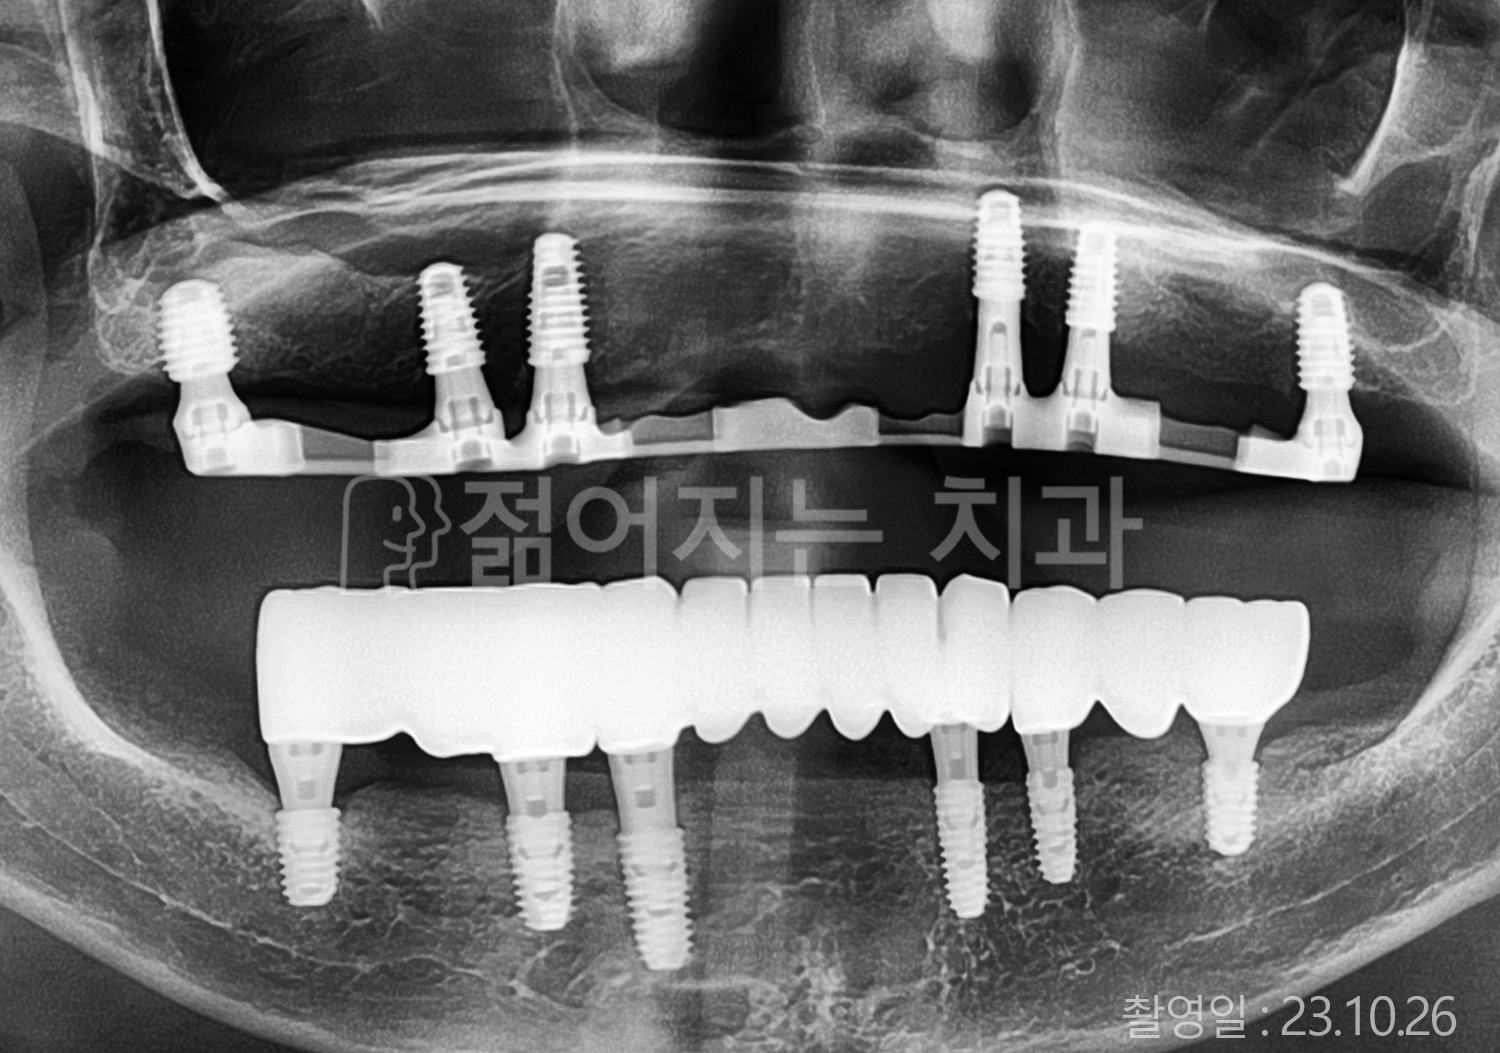

• 60대 전체치아 10개 이상 임플란트